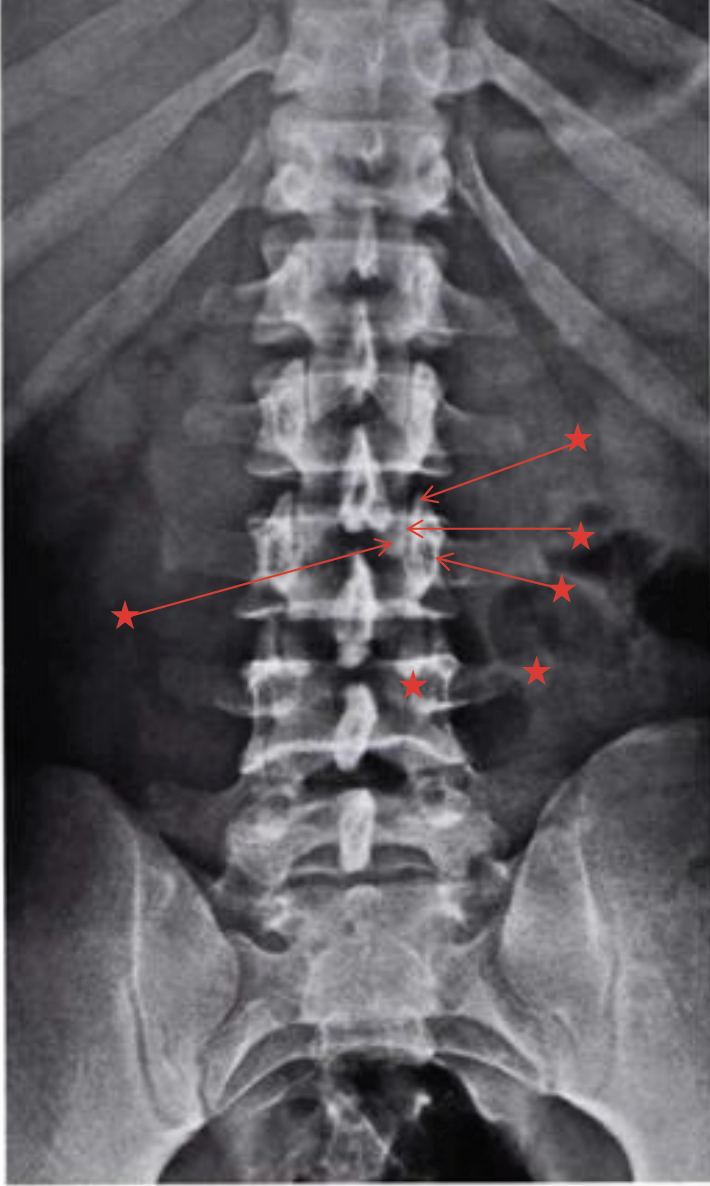

What is this view in the lumbars? Whart views are missing?

Oblique

AP (tilt 15 degree SIJ)

Lateral

Oblique on other side

L5/S1 spot (AP and Lat)